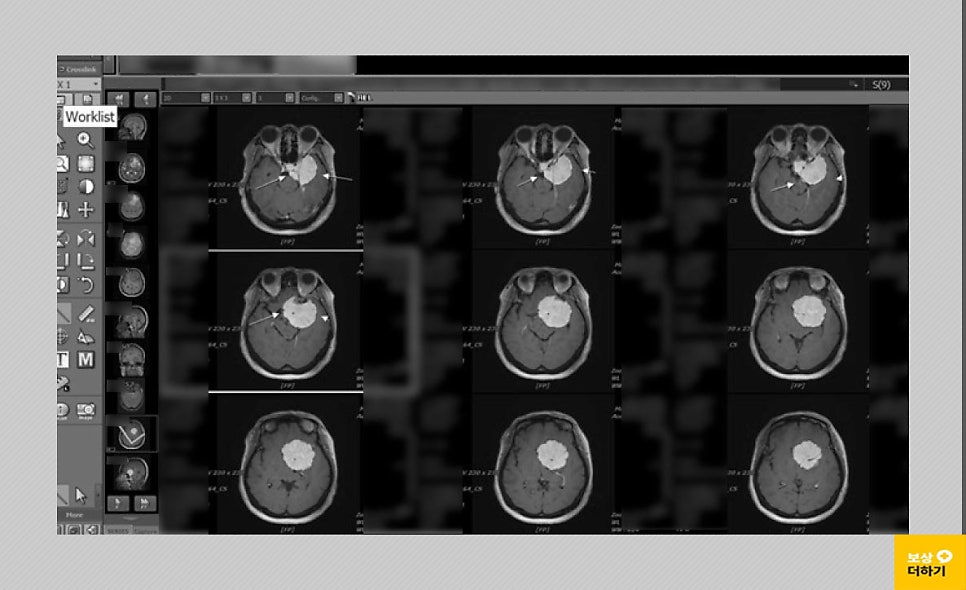

50대 여성이신 박 00 님은 어느 날부터 몸의 불편함을 느끼셨는데요. 두통과 함께 가장 이상함을 느낀 건 왼쪽 눈의 시력이 떨어지는 것이었습니다. 이에 따라 내원을 하셔서 뇌 MRI, 혈관 조영술 등 검사를 받으셨어요.

뇌종양 (뇌수막종) D32.0 (benign neoplasm of cerebral meninges) 조직 검사 결과 (meningioma, WHO grade1)

검사 결과 좌측 측두부, 접형부에 발병한 5.5cm 크기의 뇌수막종이었습니다. 시신경, 내경동맥, 뇌간을 압박해서 종양 완전 제거는 어렵고 수차례 수술, 방사선 치료가 필요하다고 판단되었습니다. * 수술: 개두술 및 두개 내 종양 절제술 받으셨습니다.

진료 소견에 의하면 좌측 내경동맥, 시신경을 침범하여 주변으로 외부종, 좌측 기저핵, 뇌간을 압박한다는 점, 종양의 완전 제거나 완치가 어렵고 재발과 악성 변화가 예상된다는 점, 임상적으로 뇌수막의 악성 신생물에 해당, C70~72로 진단할 수 있다는 것이었습니다.